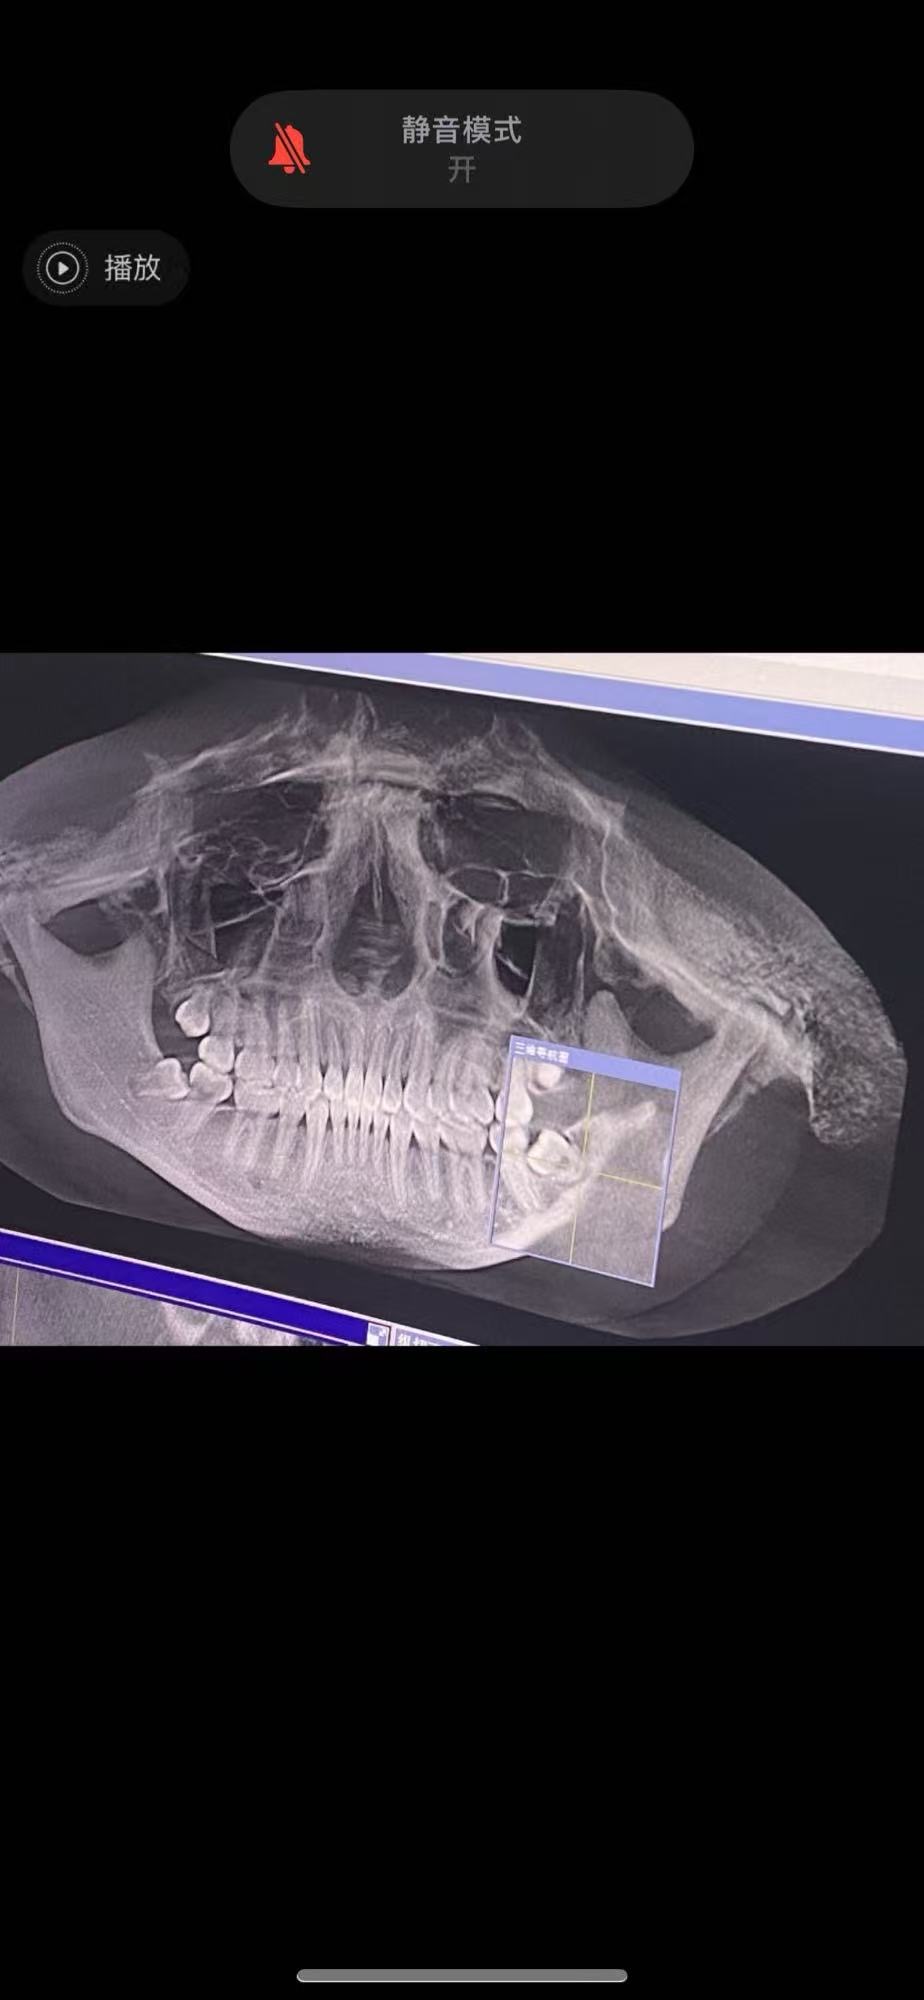

• Echo-X

12天前

去年九月拍的 医生说观察就行 让我带保持器

现在阻生智齿都冒头了 周六去看看!

感觉有必要拔了 我好不容易整的牙都歪了